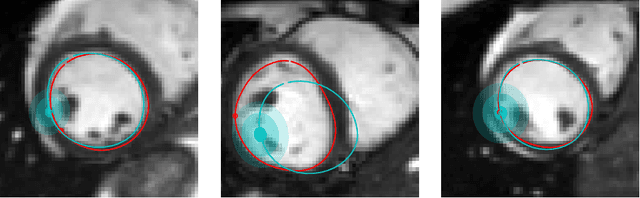

Abstract:Surface reconstruction is a vital tool in a wide range of areas of medical image analysis and clinical research. Despite the fact that many methods have proposed solutions to the reconstruction problem, most, due to their deterministic nature, do not directly address the issue of quantifying uncertainty associated with their predictions. We remedy this by proposing a novel probabilistic deep learning approach capable of simultaneous surface reconstruction and associated uncertainty prediction. The method incorporates prior shape information in the form of a principal component analysis (PCA) model. Experiments using the UK Biobank data show that our probabilistic approach outperforms an analogous deterministic PCA-based method in the task of 2D organ delineation and quantifies uncertainty by formulating distributions over predicted surface vertex positions.